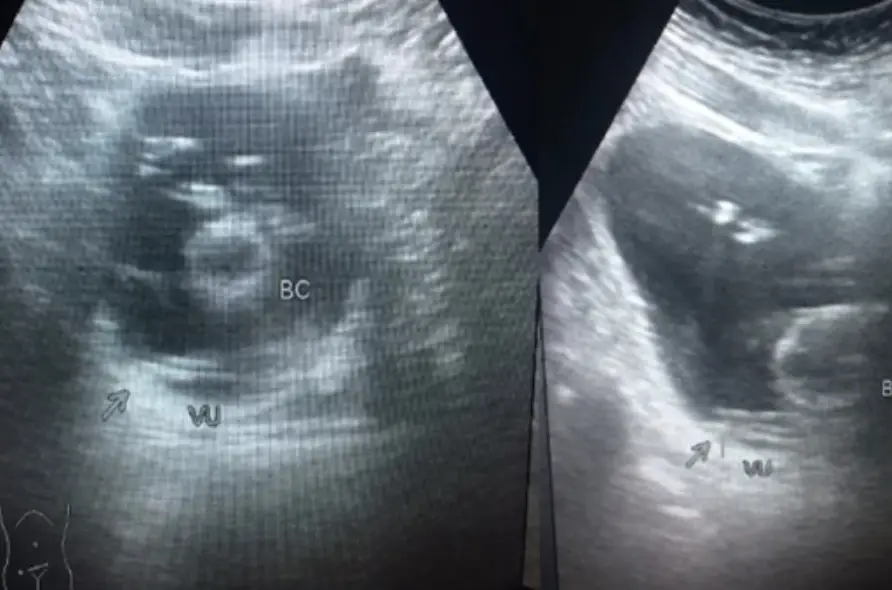

After an unsuccessful first attempt to remove the string, doctors decided to insert a camera into the man's bladder. This showed a 'black bundle of string' which meant that medics were able to use forceps after giving him local anaesthetic.

The report states: "A two-meter nylon string was extracted from the patient's bladder. The patient's postoperative complaints, vital signs, and urine production were within normal limits."